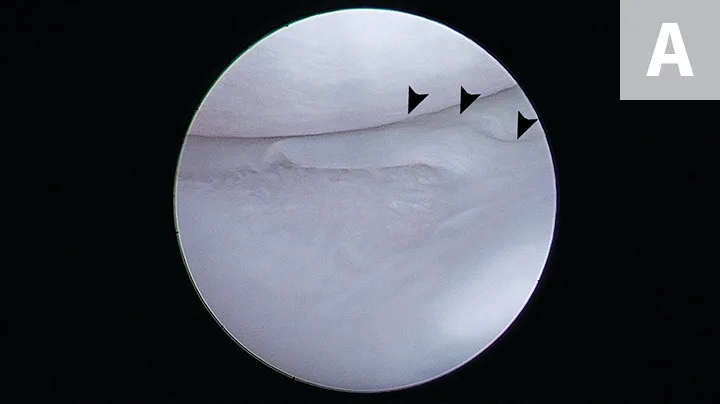

FIGURE 4A

Arthroscopic images showing a small bucket handle tear in the caudal pole of the medial meniscus (A; arrowheads). The meniscus is palpated with a meniscal probe (B; P). The torn portion of meniscus is removed with an arthroscopic shaver (C; S). After removal of the diseased meniscus, the remaining outer rim of the meniscus is left intact (D).

Treatment for meniscal tears depends on the tear location and severity.14,24,28-30 If the entire caudal pole is damaged, it should be removed via caudal pole hemi-meniscectomy.44 If only the inner rim of the caudal pole is damaged, a partial meniscectomy (ie, removal of the damaged inner rim), leaving the periphery intact and possibly preserving some of the function of the meniscus (Figure 4), can be performed. The normal meniscus is generally left in situ.